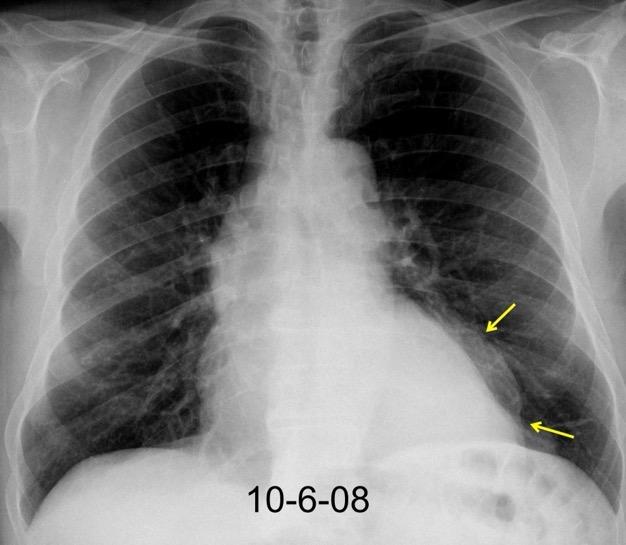

30 años

Borramiento de la banda PARA-aórtica por AdenoCa. de LII, no visible en 2005

Colapso de LII. TC: secreciones bronquiales.

Endoscopia tapón mucopurulento extraído

Borramiento parcial por Ca. epidermoide.